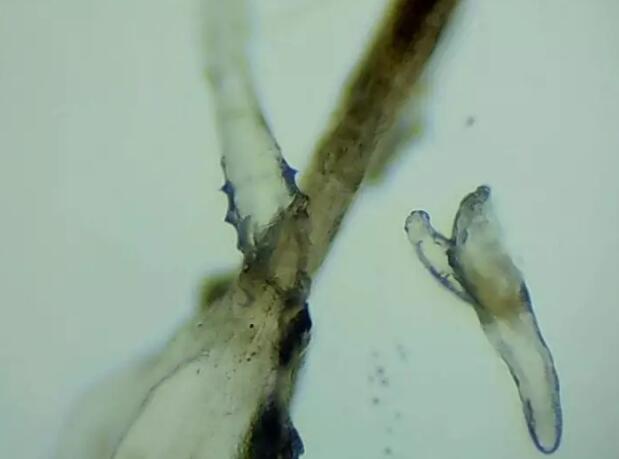

小张是一位程序员,长时间对着电脑,感觉眼干、有异物感在所难免。较近他除了眼干、难受,还发现眼睛发痒,掉落的睫毛上还会带着丝状的分泌物。刚发现时小张并没有放在心上,但当他在屏幕上看到睫毛上的螨虫时,他的心里一阵后怕,“原来我的睫毛上长着这么可怕的东西。”

厦门眼科中心蠕形螨性睑缘炎门诊张丽颖博士后介绍,人体螨虫主要有两种,一种是皮脂螨,主要寄生于皮脂腺和睑板腺内;另一种是蠕形螨,“住”在睫毛毛囊里,晚上从毛囊里爬出来,白天躲在毛囊里产卵。

据介绍,这种疾病确诊主要通过观察睫毛里的螨虫数量联合睑缘及眼表情况共同诊断。一般而言,如果12根睫毛里,有2条或是超过2条的螨虫就可以被确诊。如果检查确实发现较多的蠕形螨感染,建议加上抗螨医治。张丽颖说,发现眼睛干涩、发痒,不要自行用药,建议到医院就诊。如果长期反复多发霰粒肿,要考虑是否存在蠕形螨感染。